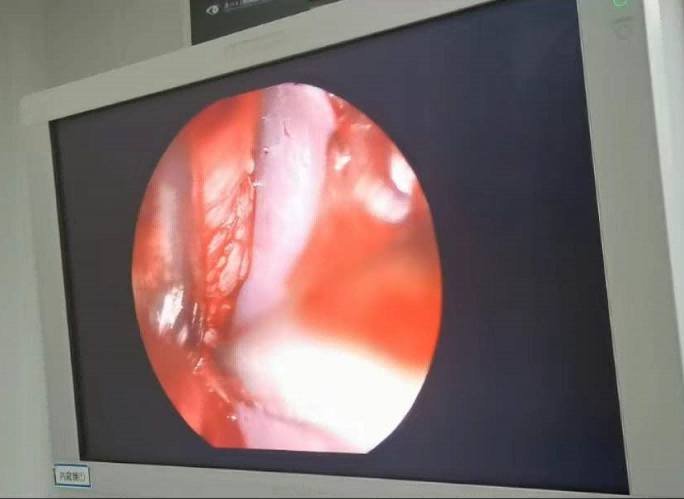

送到廈門眼科中心的時(shí)候,林老師受傷的左眼還在流血。眼整形科的鄧?yán)っ鞲敝魅吾t(yī)師緊急為他安排了“內(nèi)鏡下眶骨折修補(bǔ)+鈦網(wǎng)鈦釘植入術(shù)”。

圖為:內(nèi)鏡下眼眶骨折修補(bǔ)術(shù)

手術(shù)過程中林老師還出現(xiàn)了驚險(xiǎn)的眼球后大出血,還好鄧?yán)っ饔诰o急之中穩(wěn)住了病情,并順利完成了手術(shù)。術(shù)后第二天,林老師的術(shù)后反應(yīng)就很輕,恢復(fù)良好,他一邊感謝著鄧?yán)っ鞯?ldquo;救命之恩”,一邊自嘲著自己示范了個“反面教材”。